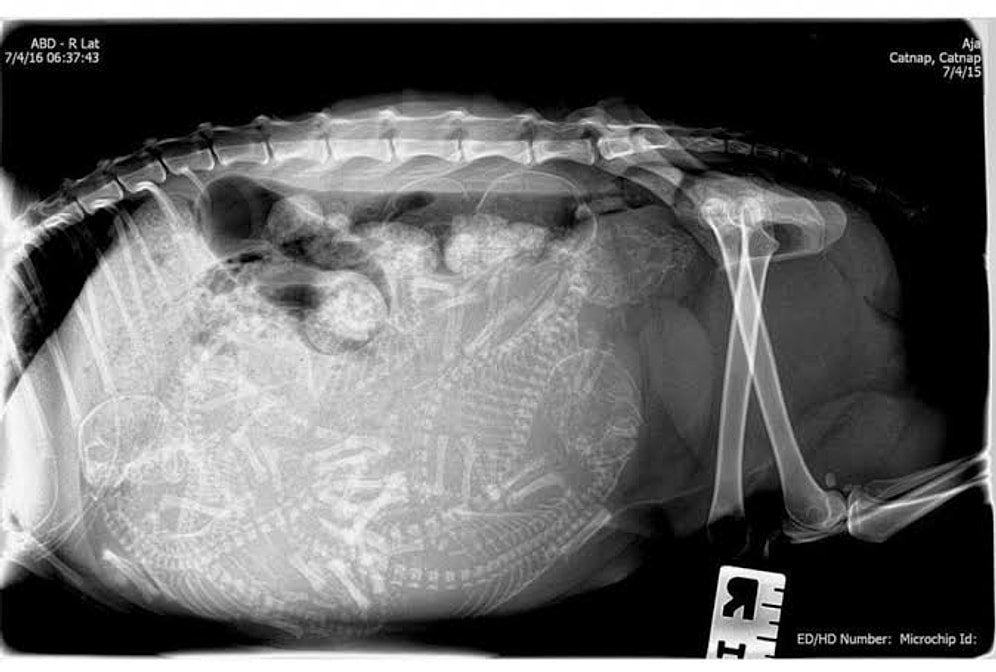

Удивительные рентген-снимки беременных животных: теперь вы видели все!

Вы когда-нибудь видели зародышей змеи, акулы, черепашек? Скорее всего, нет. Рентген существует уже давно, но не каждый день ветеринары готовы поделиться 'интимными' снимками животных, готовых принести потомство.Сегодня нам выпала такая возможность. Поверьте, вы узнаете для себя много нового!